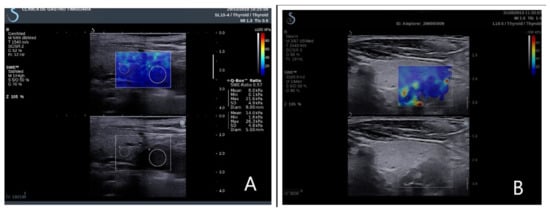

Quantitative information, described as the elasticity index (EI), was obtained on the frozen elastogram image using a quantification box (Q-box), placed in the regions of interest (ROI) (Figure 2). The elasticity parameters are displayed after software computing evaluating the mean SWE, minimum SWE, maximum SWE, and standard deviation of elasticity value. All measurements are numerically expressed in kilopascals (kPa). As there are no scale settings for the parathyroid examination, a thyroid scale was used (0–100 kPa).

Figure 2. Elasticity index parathyroid and thyroid tissue. (A) Right inferior parathyroid adenoma in primary hyperparathyroidism; (B) left inferior parathyroid hyperplasia in secondary hyperparathyroidism.